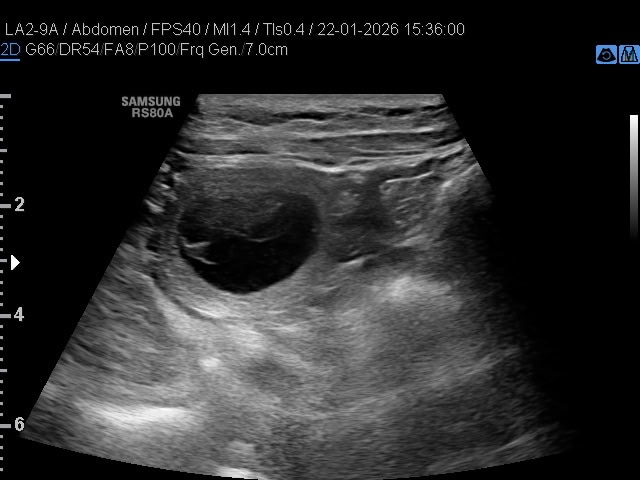

Gistermiddag was op dag 25 de echo van Nayeli. Dat ze drachtig zou zijn dat had ik wel verwacht gezien haar gedragingen maar ik had ook verwacht dat er wel een behoorlijk aantal pupjes in haar buikje zou zitten en dat is niet zo: Nayeli gaat een klein nestje krijgen. Ik ben doorgaans grote en hele grote nesten gewend dus dit is ook weer eens iets anders. Hieronder 2 afbeeldingen van de echo van gister: